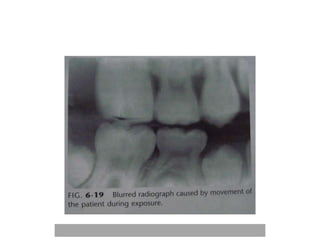

Radiographic blurring iscaused by- • Image receptor blurring • Motion blurring • Geometric blurring

Image receptor blurring •Intra-oral films-grain size • Intensifying screens • Double emulsion film